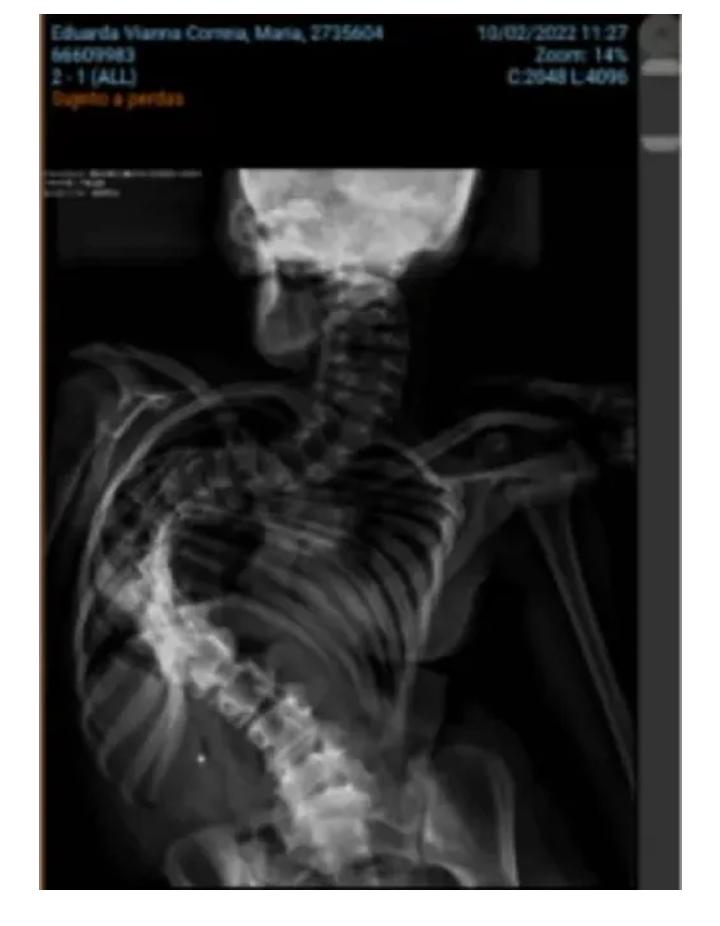

A Maria Eduarda, ou Dudinha como é mais conhecida, tem 13 anos, é morado do interior do Munícipio de Taquara – RS, e precisa urgentemente de uma cirurgia. A Dudinha sofre com o avanço da doença conhecida como Síndrome de Cornélia de Lange. A doença vem progredindo atingindo sua coluna, o que está fazendo com que a caixa torácica de Dudinha se altere comprimindo seus órgãos; o que infelizmente pode levar à morte da menina.

A família corre contra o tempo, e já foi alertada que a espera pela cirurgia pelo Sistema Único de Saúde pode demorar. E a família de Maria Eduarda teme que a menina não tenha esse tempo. É preciso conter a compressão que sua caixa torácica tem feito afetando seus órgãos o mais rápido possível.